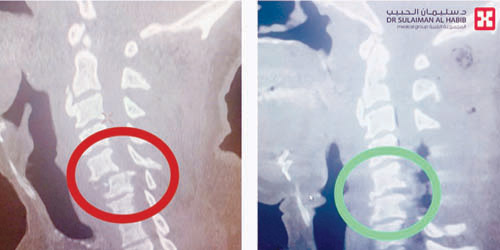

وأضاف د. محسن أنه تم إجراء فحوصات شاملة للمريض أظهرت وجود كسور متعددة وإزاحة شديدة في الفقرتين الرقبيتين الخامسة والسادسة، إضافة إلى إصابة شديدة في النخاع الشوكي وقرَّر الفريق الطبي إجراء عملية جراحية تم فيها رفع الضغط عن الحبل الشوكي مع تثبيت الكسور وزراعة عظم صناعي، ومضت العملية التي استمرت لـ»4» ساعات، بسلاسة ووفقاً للخطة العلاجية، وتكلَّلت -ولله الحمد - بالنجاح التام، حيث استعاد العمود الفقري استقامته، واستطاع المريض تحريك أطرافه العلوية بعد العملية مباشرة، وتحسنت حالة المريض باطراد خلال فترة التنويم وغادر المستشفى بحالة صحية جيدة.

وأوضح د. محسن أن «تثبيت الفقرات الرقبية في العادة يتم من الأمام، لكن في هذه العملية جرى التثبيت من الخلف، وتعتبر هذه التقنية جديدة، وتتميز بأنها تمكّن الطبيب من إعادة الخلع بدقة أكبر وبالتالي تحقيق التئام أسرع للكسر والخلع».